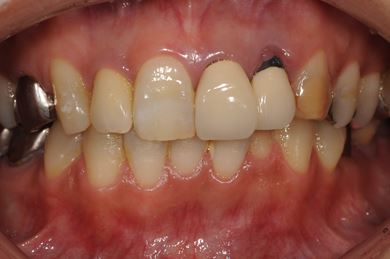

インプラントの症例写真 IMPLANT

骨再生インプラント治療+セラミック治療

| カテゴリー | 【インプラント治療】【セラミック治療】 | ||||||||||||||||||||||||||||||||

| 性別/年齢 | 女性 / 48歳 | ||||||||||||||||||||||||||||||||

| 主訴 | 他の歯科で、前歯の差し歯が折れたところにインプラントをすすめられているので、費用や期間など知りたい。 | ||||||||||||||||||||||||||||||||

| 治療方針 | 骨再生法により、インプラント治療を可能にする。 | ||||||||||||||||||||||||||||||||

| 治療内容 | インプラント1本、メタルボンドセラミッククラウン2本、GBR | ||||||||||||||||||||||||||||||||

| 総治療費 | 618,660円 | ||||||||||||||||||||||||||||||||

| 治療期間 | 9ヶ月 |